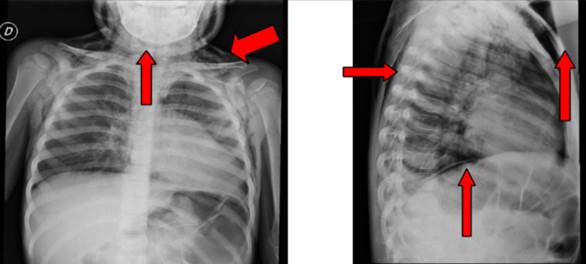

Con planteo inicial de neumotórax y lesión de la vía aérea, se realiza radiografía de tórax (RxTx), que evidencia enfisema subcutáneo extenso (Figura 1).

Figura 1: Radiografía de tórax de frente y perfil donde se evidencia el extenso enfisema subcutáneo, señalado por las flechas.